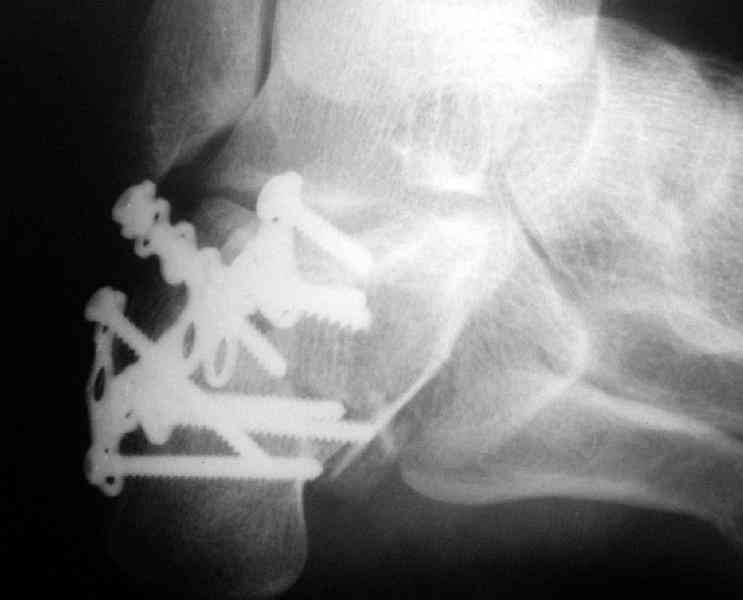

Its a comminuted one.

I would have a CT prior 2 surgery(If u have to postpone a surgery for it - I would operate without one)

I myself would reduce it with EX-FIX and depending on the result would consider a plate on the table.

MOST OF MY COLLEGUES WOULD OPEN IT LATERALLY( a flap) and having a proper reduction would put a plate.

Сустав похоже интактен, киста под вопросом,

Перелом безусловно внутрисуставной. Киста-не киста принципиального значения не имеет.